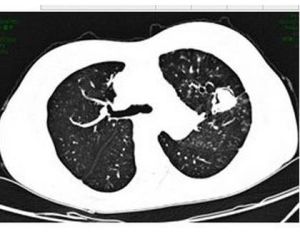

7.胸部X線檢查可呈斑點狀、結節狀或雲絮狀陰影。麴黴球典型的徵象為密度均勻似球狀,其上方有薄壁半月形透亮區,麴黴球可隨體位變動而變動,呈“鐘形陰影”。好發部位為肺上葉.

麴黴球其他輔助檢查:X線上麴黴球表現為肺空洞或胸膜腔內圓形緻密陰影,其邊緣有透光暈影。若空腔較大,尚可見球形陰影有蒂與洞壁相連,形如鐘擺,球形陰影可隨體位變化而改變形態。如果空洞較小,球形病灶填充了大部分空腔,其暈影很小,僅呈一狹長的半月形透亮帶。有學者曾在2例X線平片、體層片和支氣管造影片均無陽性發現的隱源性大咯血患者套用支氣管動脈造影定位後行手術治療,病理髮現1cm左右的細小支氣管囊腫繼發麴黴球。胸部CT檢查特別是高分辨CT的套用為發現細小麴黴球和鑑別診斷提供了有用技術。